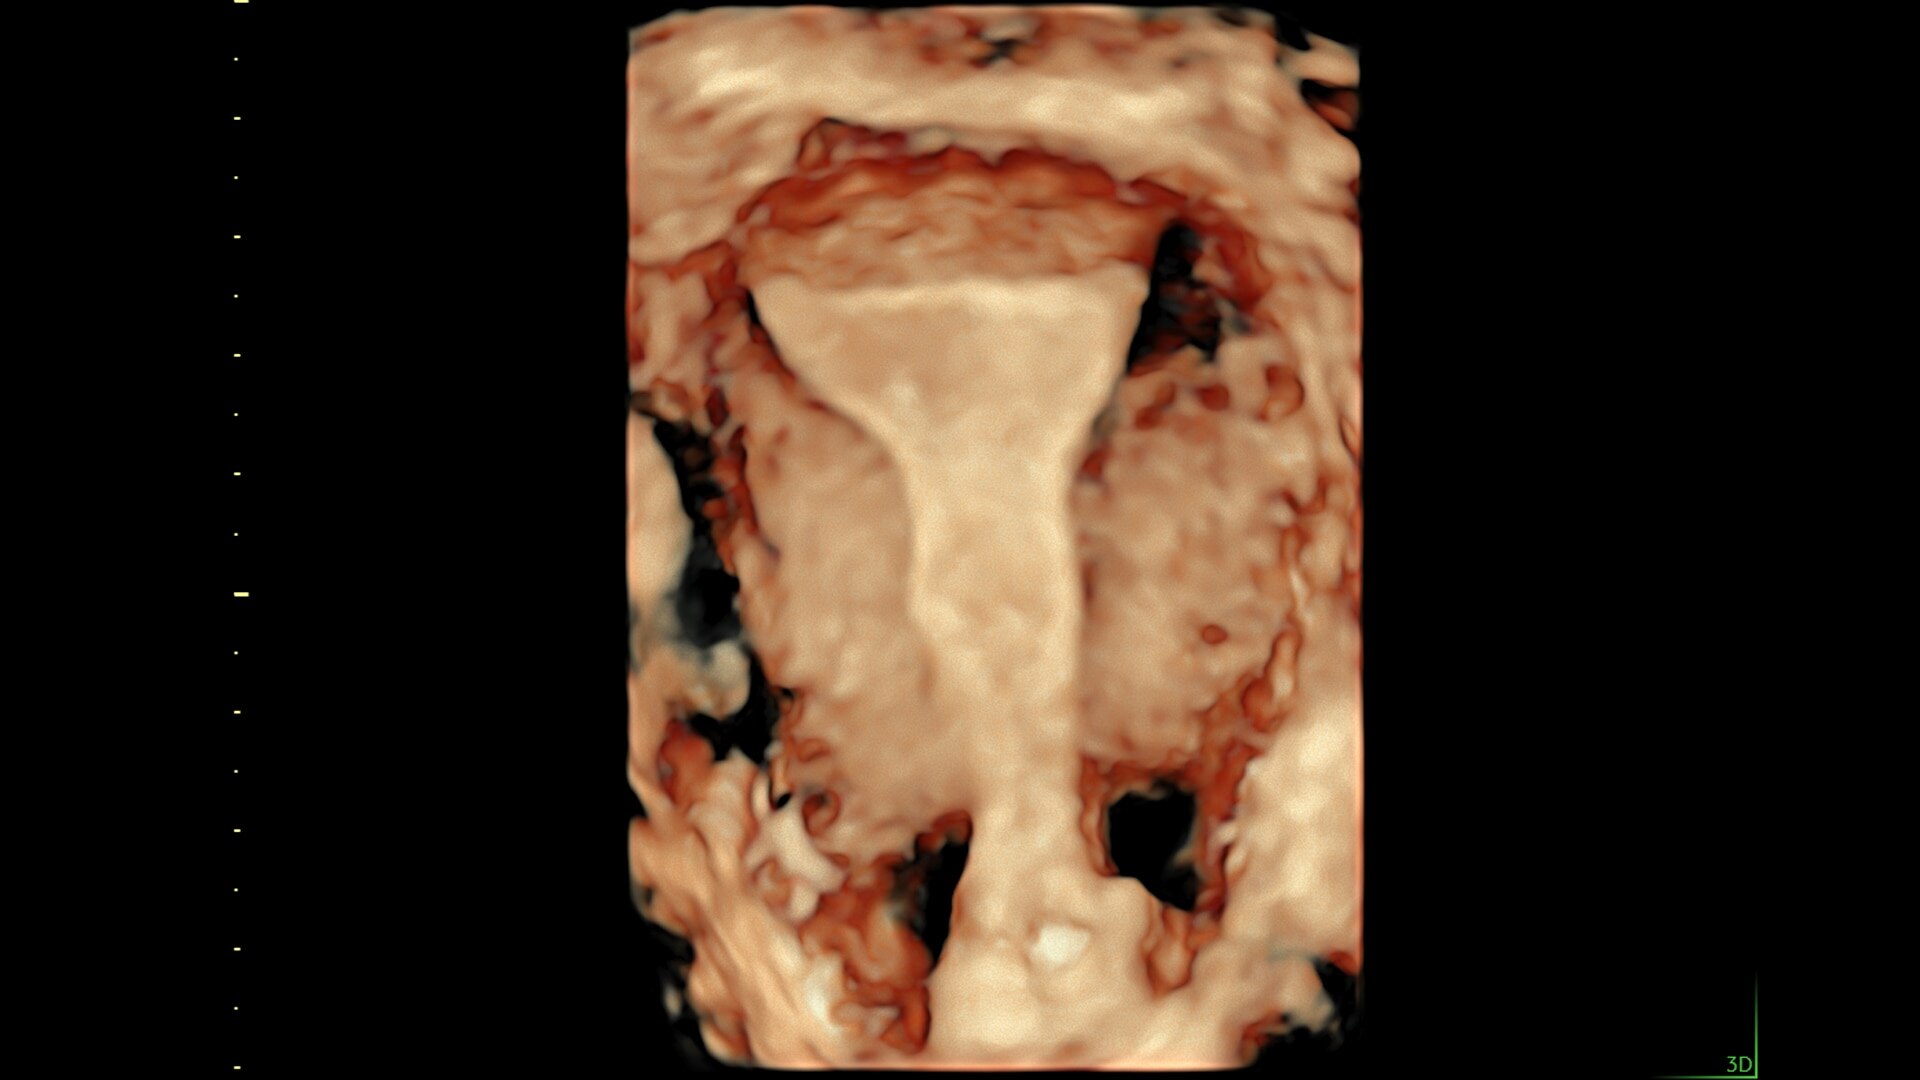

Fast, easy 3D-like blood flow visualization

Next level color Doppler delivers exceptional sensitivity for easy, fast visualization of blood flow, revealing even the tiniest vessels.

3-radiantflow-clinical-image-ci-en